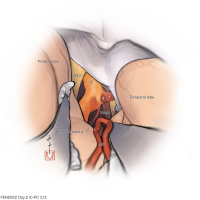

OPExPARK20220130コンテンツシリーズ